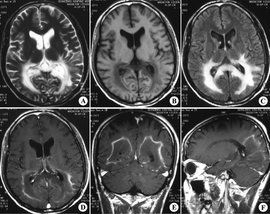

(3) 影像學表現

CT表現為局限於腦白質的低密度蝶形病灶;MRI優於CT,能顯示視覺、聽覺傳導通路和運動傳導通路上的病灶。

顱腦MRI具有特徵性改變,MRI的表現可以領先或與ALD症狀同時出現,並隨著病情的發展而發展。

表現為對稱性位於雙側頂枕區白質長Tl長T2號,周邊呈指狀,胼胝體壓部早期受累,呈“蝶翼狀”,是ALD所特有的,其他腦白質病少見;ALD的一個顯著特點是病變由後向前進展,逐一累及枕、頂、顳、額葉;可累及腦幹皮質脊髓束,皮質下U形纖維免於受累;增強掃描病灶周邊強化,提示處於活動期;晚期增強後無強化,多伴有腦萎縮。ALD的不同階段在頭部MRI上表現不同,可藉此作為治療轉歸和判斷預後的指標。